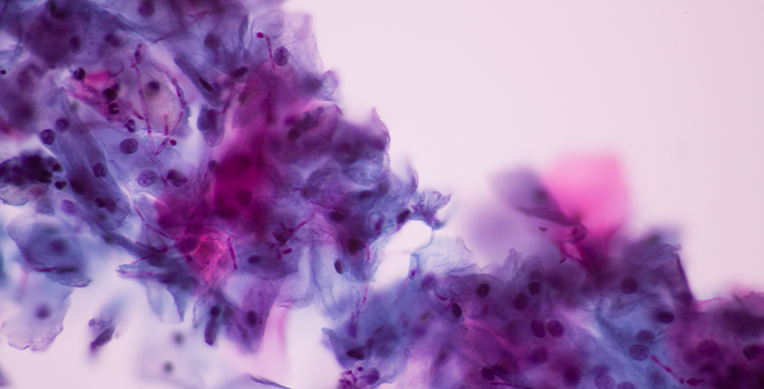

Cuando hablamos de qué es candidiasis vaginal, estamos hablando de una infección generada por hongos vaginales. Esta se da porque un hongo que está presente de forma normal en la zona V, y que es conocido como Cándida Albicans, se reproduce de manera acelerada, generando una infección.